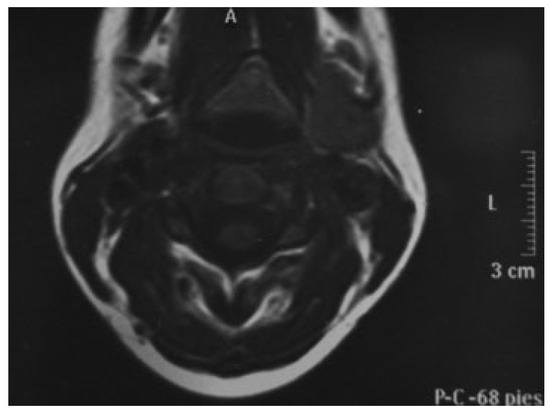

The follow-up was uneventful but 2 years later in October 2007, she presented complaining of swelling slightly painful on the right side of his neck. FNA cytology of the cervical mass suggested mixed tumor of submaxillary gland. Computed tomography (CT) revealed postsurgical changes in right parotid region without suggestive signs of recurrence. In right submaxillary cell, a well-defined mass of 2 cm surrounded by a fibrous pseudocapsule of varying appears (Figure 1). The patient was operated and discharged from hospital 2 days later. The final diagnosis was pleomorphic adenoma of submaxillary gland. Histopathological investigation reported that the lesion had typical features of pleomorphic adenomas with ducts and cords of cells lying within chondromyxoid stroma.

Figure 1. In right submaxillary cell, a well-defined mass of 2 cm surrounded by a fibrous pseudocapsule of varying appears.